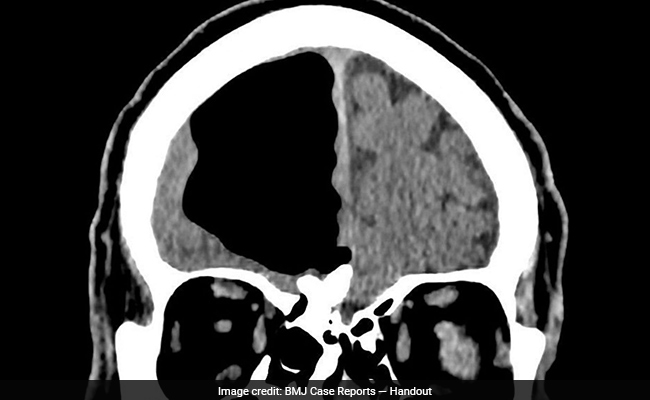

Doctors Find Air Pocket Where Part Of Man's Brain Should Be

- Tuesday March 13, 2018

- World News | Amy B Wang, The Washington Post

The 84-year-old man arrived in the emergency room with complaints that weren't uncommon for a patient his age. He had reported feeling unsteady over the past several months, culminating in repeated falls in recent weeks. In the three days leading up to his hospital visit, his left arm and leg had noticeably weakened.